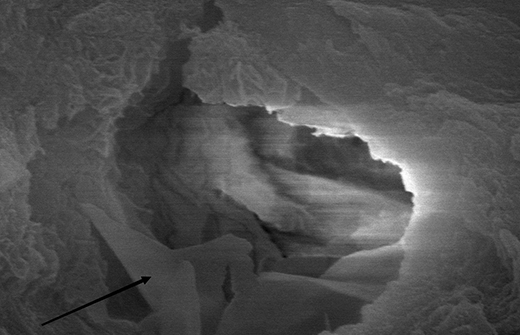

C-Root SP是預混合的、可即刻應用的、可注射的、遇水凝固的硅酸鹽類生物活性陶瓷糊劑材料,主要成分為硅酸鍶、氧化鋯、磷酸鈣、氫氧化鈣,用于根管的密封和永久充填,適合單尖法、側壓法和熱牙膠法。 C-Root SP為世界口腔醫生提供一個“鍶生物陶瓷”的新選擇! >>>